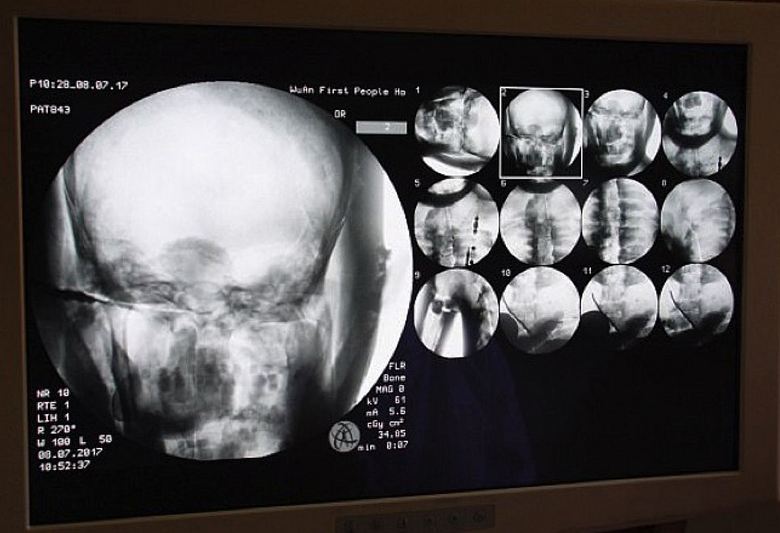

Vědci ochotně souhlasili, protože se o to sami zajímali tato zajímavá studie. A 8. července tohoto roku, přímo v chrámu Dinghui, byla provedena tomografie starověké buddhistické mumie mnich. Lékaři sem přivezli potřebné vybavení a utratili skenování vnitřního obsahu mumie. Byli šokováni výhradně všechno, to znamená nejen učenci, ale také mniši, poutníci, kteří se shromáždili na tomto nebývalém stavu pro klášter událost, samozřejmě, a mediální pracovníci. Ukázalo se, že klouby, kosti a zuby tisíciletého mnicha Tsa Xian jsou jako ty, které žijí osoba. Navíc byl jeho mozek dokonale zachován.

Je to neuvěřitelné, poznamenal doktor Wu. Yongqing (Wu Yongqing), který přímo provedl tomografii mumie. Nemůžu ani uvěřit, jak hlavní části člověka balzamovaný před více než tisíci lety, zachovalý v “zdravý” stav, dokonce i mozek! Ale samotní mniši nejsou nevidí v tom nic nadpřirozeného, jsou si jisti, že Mistr Tsy Xian nezemřel vůbec, jednoduše vstoupil do stavu samádhi který se jednoho dne jistě probudí. Koneckonců, skenování mumie ukázáno: jeho tělo je připraveno na nový život …